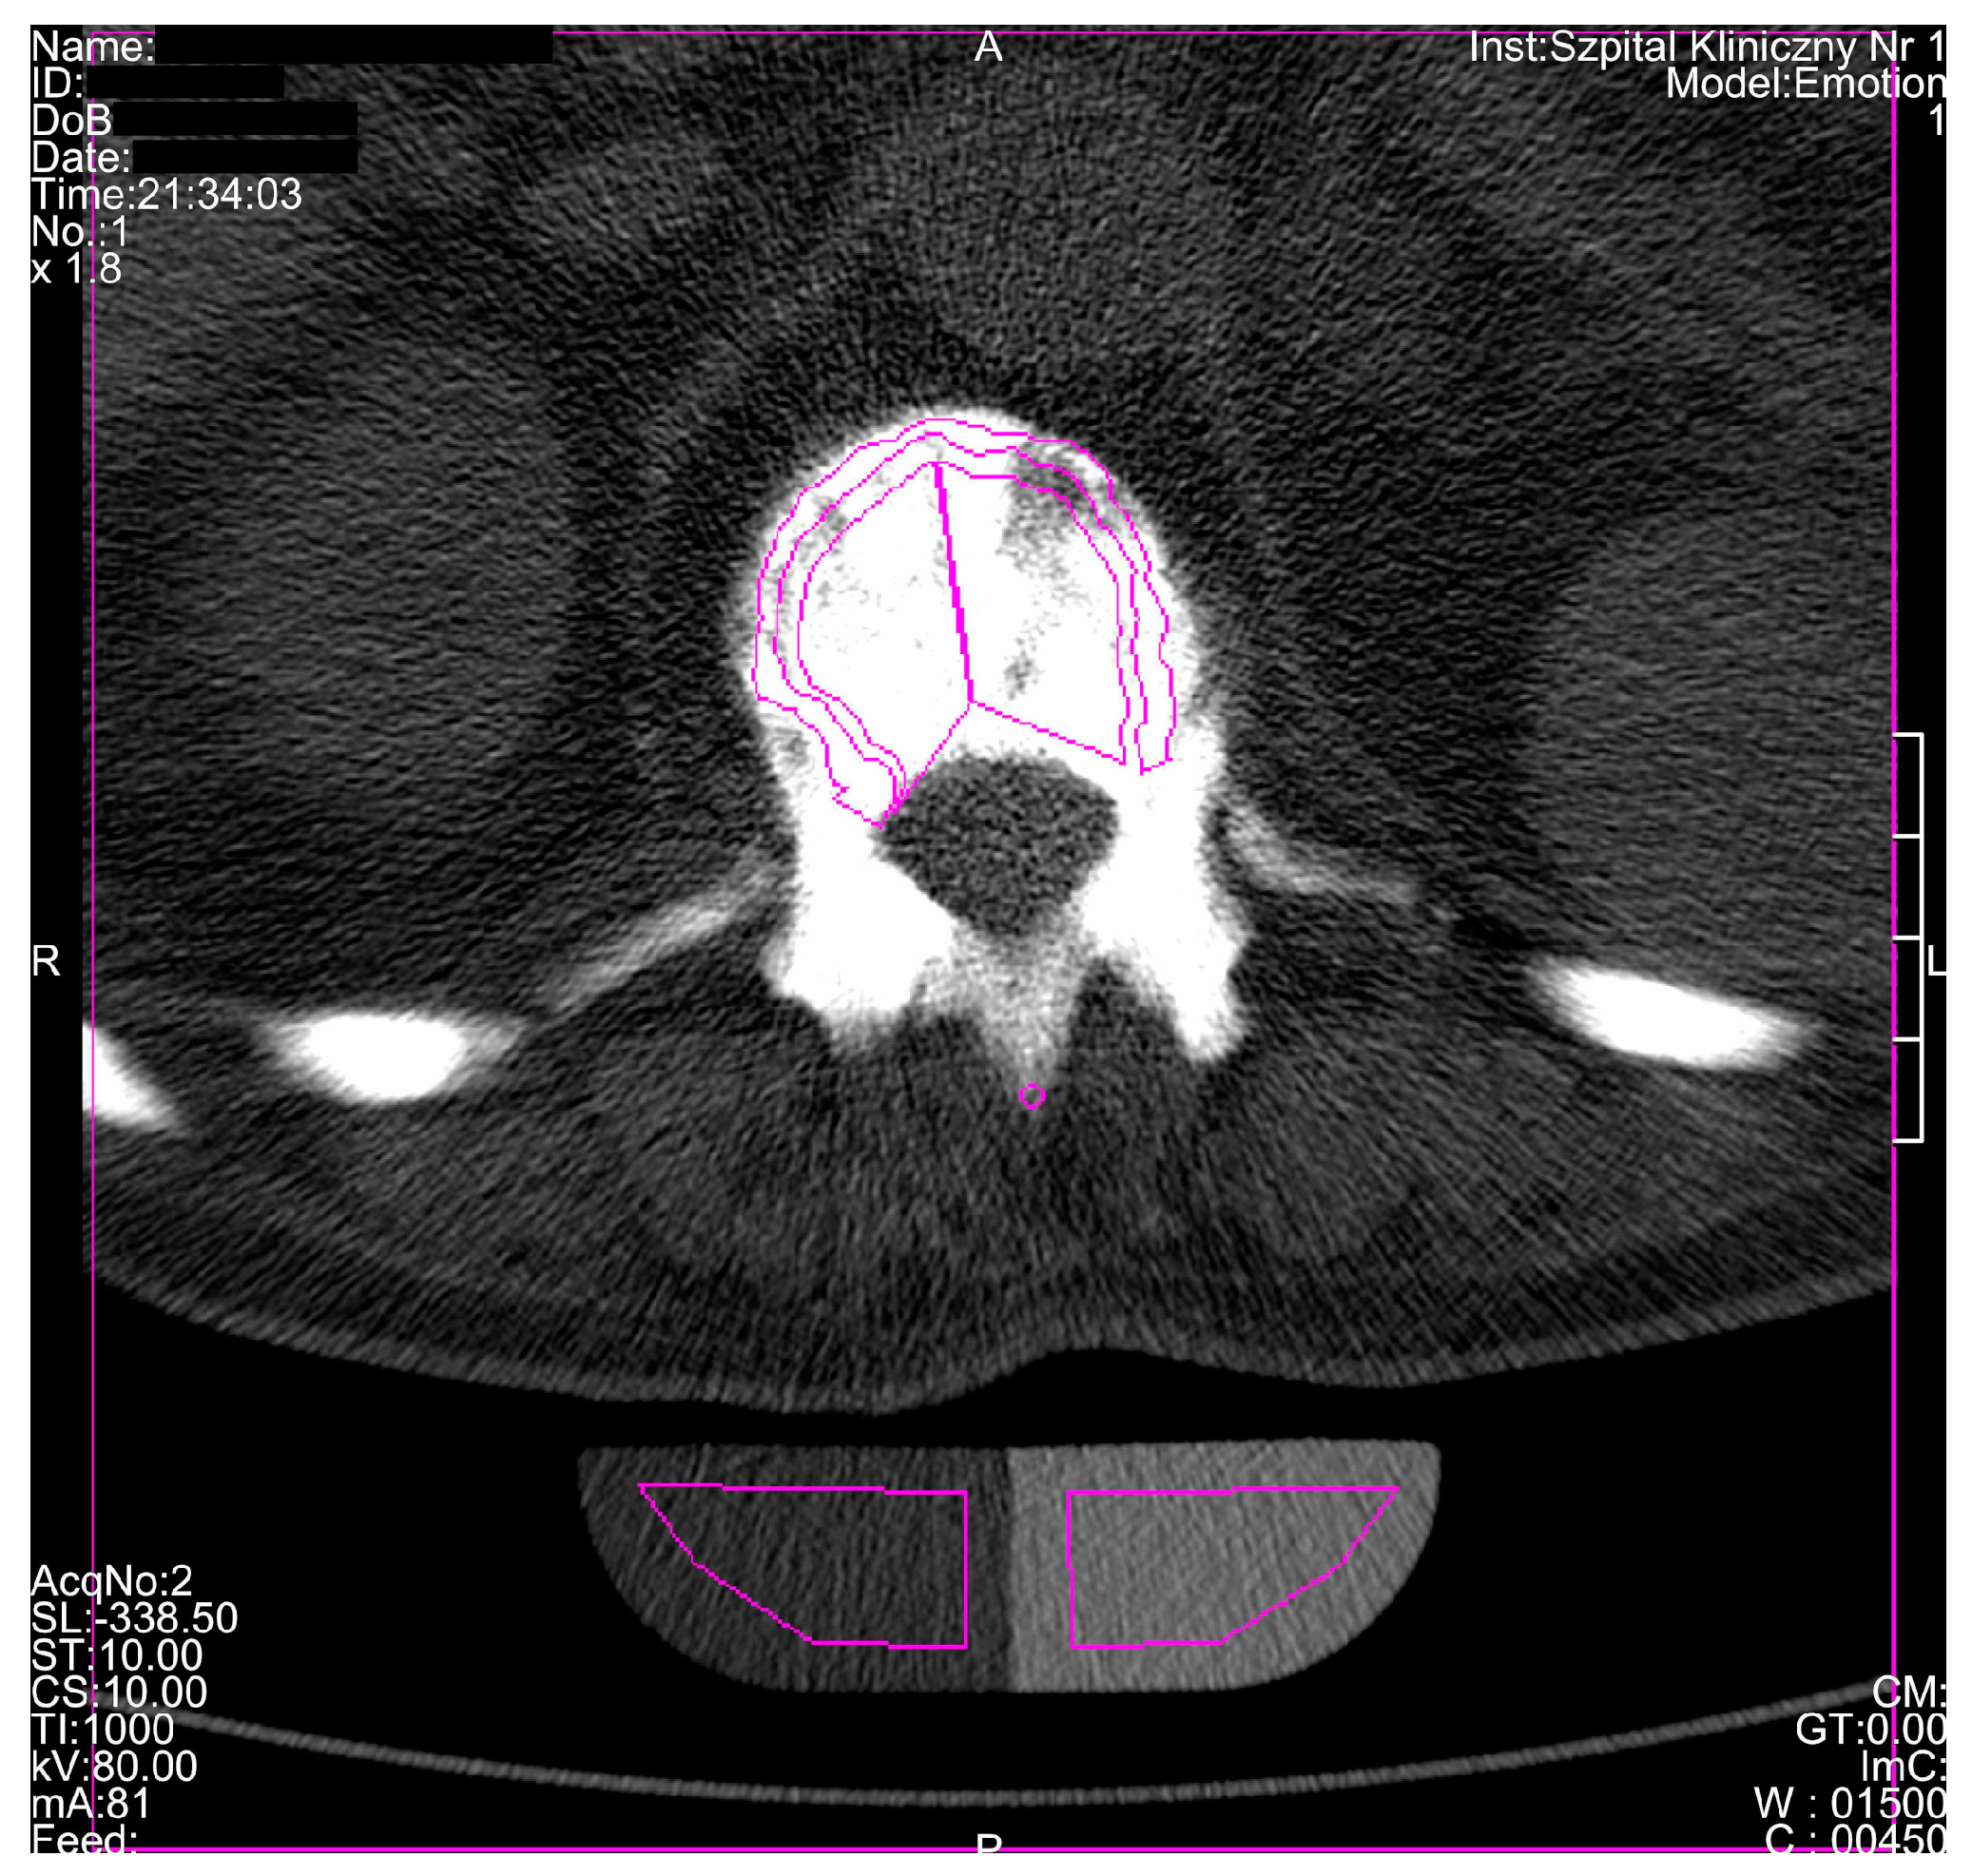

| Investigated Bone | TbCa-HA (mg Ca-HA/mL) | CbCa-HA (mg Ca-HA/mL) | T-Score | Z-Score | vBMD (g/cm3) |

|---|---|---|---|---|---|

| Spine | |||||

| Th12 vertebra | 834.1 | 800.3 | - | - | - |

| L1 vertebra | 918.5 | 813.5 | - | - | - |

| L2 vertebra | 927.6 | 861.5 | - | - | - |

| L3 vertebra | 860.6 | 816.4 | - | - | 1.936 |

| L4 vertebra | 865.7 | 846.6 | - | - | 1.943 |

| L5 vertebra | 1039.8 | 833.7 | - | - | 1.912 |

| Th12-L2 vertebrae | 893.4 | 825.1 | 27.12 | 31.00 | - |

| L3-L5 vertebrae | 922.0 | 832.2 | 28.20 | 32.08 | 1.930 |

| L1-L5 vertebrae | 922.4 | 834.3 | - | - | - |

| Reference value for 80-year-old man | 71.8 | - | - | - | - |

| C1 vertebra | - | - | - | - | 1.987 |

| C2 vertebra | - | - | - | - | 2.107 |

| C3 vertebra | - | - | - | - | 2.010 |

| Pelvis | |||||

| Right ilium | - | - | - | - | 1.954 |

| Left ilium | - | - | - | - | 1.924 |

| Cranium | |||||

| 50% of cranium height | - | - | - | - | 2.111 |

| Mandible | |||||

| Mandibular body | - | - | - | - | 1.812 |

| Right ramus | - | - | - | - | 1.678 |

| Left ramus | - | - | - | - | 1.757 |

| Hyoid | |||||

| Middle part | - | - | - | - | 2.135 |

| Right part | - | - | - | - | 1.731 |

| Left part | - | - | - | - | 1.840 |